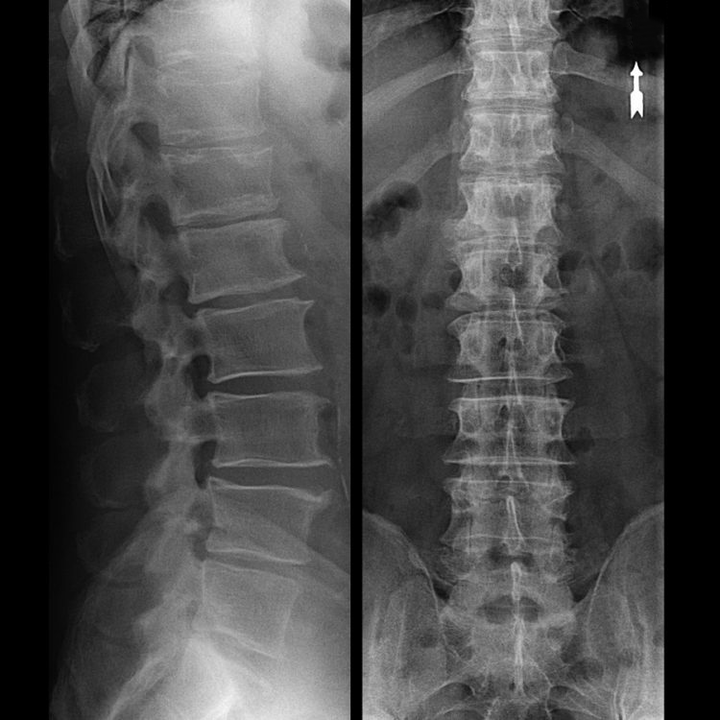

Unha "radiografía" da columna cervical, e mesmo con probas funcionais de flexión e extensión, non mostra cartilaxe, xa que o seu tecido transmite raios X. A pesar diso, en función da localización das vértebras, pódense extraer conclusións xerais sobre a altura dos discos intervertebrais, o endereitamento xeral da curvatura fisiolóxica do pescozo - lordose, así como a presenza de crecementos marxinais nas vértebras con irritación prolongada das súas superficies por discos intervertebrais fráxiles e deshidratados. As probas funcionais poden confirmar o diagnóstico de inestabilidade na columna cervical.

Dado que os propios discos só se poden ver mediante TC ou resonancia magnética, a resonancia magnética e a tomografía computarizada de raios X están indicadas para aclarar a estrutura interna da cartilaxe e formacións como protuberancias e hernias. Así, coa axuda destes métodos, faise un diagnóstico con precisión e o resultado da tomografía é unha indicación, e mesmo unha guía tópica, para o tratamento cirúrxico dunha hernia no departamento de neurocirurxía.